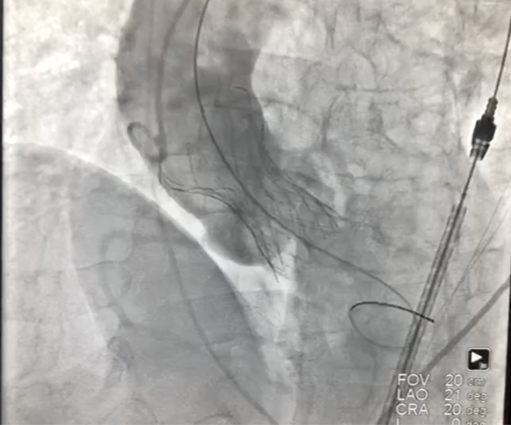

术后心电监护未见传导阻滞,心超提示人工主动脉瓣工作良好,瓣叶启闭正常,主动脉瓣峰值流速2 m/s,平均跨瓣压差6 mmHg,轻度瓣周漏。

图片

主动脉根部造影示瓣膜位置合适(深度2 mm),轻度瓣周漏。遂释放瓣膜,撤回脑保护装置,手术圆满成功